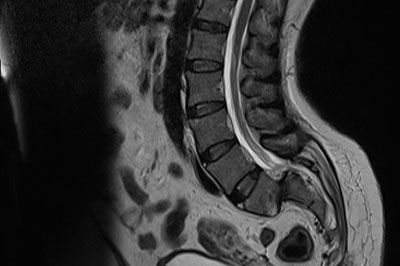

Spondylodiscitis

Infection occuring in the disc space is called as spondylodiscitis. Most commonly the infection is due to tuberculosis and rerely by other bacterias and fungus...

read more